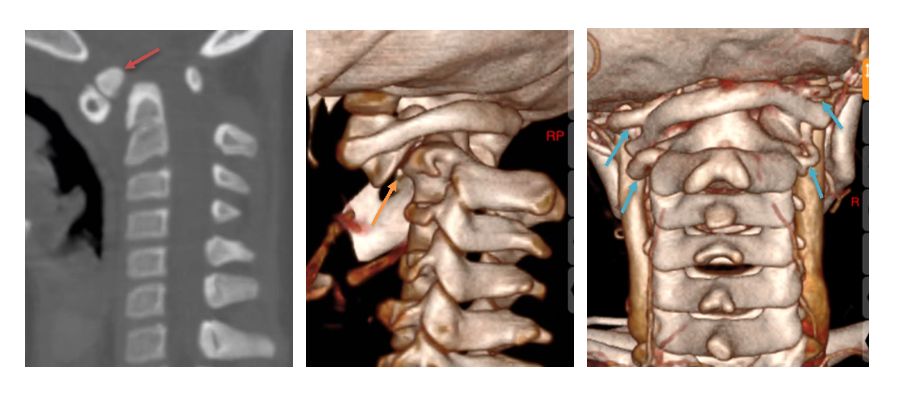

面对挑战,许正伟主任团队在西安市红会医院脊柱病医院院长闫亮、学科带头人贺宝荣主任带领下,为康康制定了周密的个性化方案。术前,三维椎动脉 CTA 精准「测绘」出脱位的详情与椎动脉的走向(图二及图三)。由于患儿无法配合常规牵引,团队决定在术中实施高难度的颅骨牵引复位。

手术日,在麻醉与神经电生理监测团队的全程护航下,主刀医生许正伟主任首先巧妙利用颅骨牵引,为完全脱位的关节实现了初步松解与部分复位。随后,在高端术中导航系统( S 8 )的实时引导下,将椎弓根螺钉精准、安全地置入寰椎与枢椎的微小椎弓根内。利用螺钉提供的稳固杠杆,脱位的关节被轻柔而坚定地「推」回了正常解剖位置,实现了完美复位。最后,取自患儿自身的髂骨块被植入后方,为永久性骨融合打下基础。